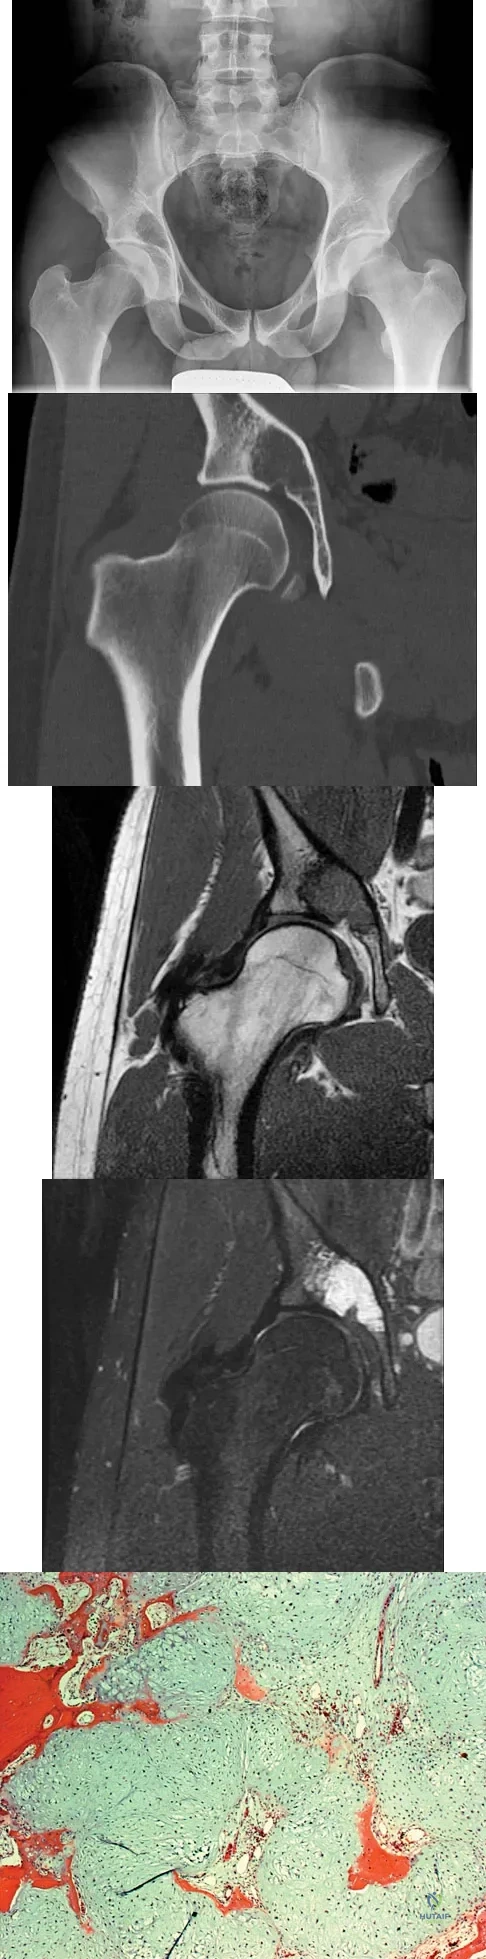

A 73-year-old man stepped off a street curb and felt a crack in his left hip. He is now unable to bear weight. A radiograph is shown in Figure 54a. Biopsy specimens are shown in Figures 54b and 54c. What is the most likely diagnosis?

A 65-year-old man has a painful right hip mass that has been growing for several years. A radiograph, CT scan, and photomicrograph are shown in Figures 56a through 56c. What is the most appropriate treatment?

Figures 61a and 61b show the CT and MRI scans of a 40-year-old man who has hip pain. He undergoes total hip arthroplasty and curettage and cementation of the lesion as shown in Figure 61c. Histopathologic photomicrographs of the curettage specimen are shown in Figures 61d and 61e. What is the best course of treatment?